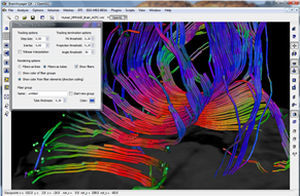

Diffusor Tension Imaging (DTI) module to analyze diffusion-weighted MRI data including calculation of FA maps, fiber tracking and FA group comparisons.